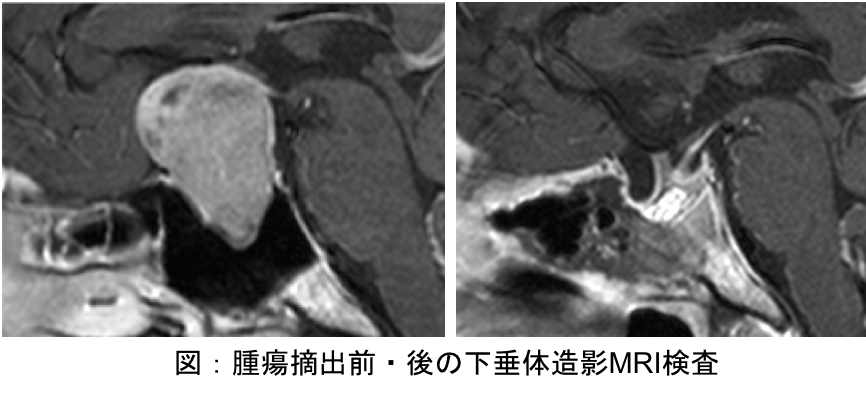

当科では、間脳・下垂体疾患の診断・治療に豊富な経験を有する専門医が診療に取り組んでいます。特に下垂体腺腫、ラトケ囊胞などのトルコ鞍部に発生する疾患に対しては、主に内視鏡を用いた経鼻手術(内視鏡下経鼻的下垂体腫瘍摘出術)を積極的に行っており、さらに、難治性の病気に対しては、薬物治療(ホルモン療法)や放射線治療などを組み合わせた集学的治療を一貫して行っており、良好な成績を得ています。

下垂体腺腫を診断する際、まず造影剤を使ったMRI検査を行います。通常の水平断のみならず、冠状断や矢状断なども含めて脳内を観察し、腫瘍の大きさや進展方向、また視神経や周囲の血管および正常下垂体との関係を詳しく調べます。微小腺腫と言われる直径1cm未満の小さな腺腫では、ダイナミック法を駆使して的確に診断します。

プロラクチン産生腺腫(プロラクチノーマ)を除く下垂体腺腫に対しては、基本的に内視鏡下経鼻的下垂体腫瘍摘出術を行います。当施設では、最新の内視鏡手術装置および手術用ナビゲーションを常備しており、狭い術野でも安全かつ確実に手術を行うことが可能です。最近では高齢の患者さんも増えており、手術前には内科や麻酔科とも十分相談し耐術能についてもきちんと評価した上で手術を受けていただきます。この手術では、鼻孔から内視鏡を挿入し、蝶形骨洞(副鼻腔の一部)を経由してトルコ鞍という腫瘍が収まっている頭蓋骨のくぼみに到達します。この骨に1.0〜1.5cm程度の小さな穴を開け、正常下垂体や周囲の重要な血管(海綿静脈洞や内頚動脈など)を傷つけないようにしながら腫瘍を最大限に摘出します。摘出後の空洞には、通常右下腹部から採取した脂肪片を埋めた後、手術用の接着剤(フィブリン糊)でしっかりと固定します。最後に鼻腔内をタンポンガーゼでパッキングします。この方法は、脳を直接触らないため比較的安全な手術と考えますが、髄液漏、尿崩症や鼻出血などの合併症があります。